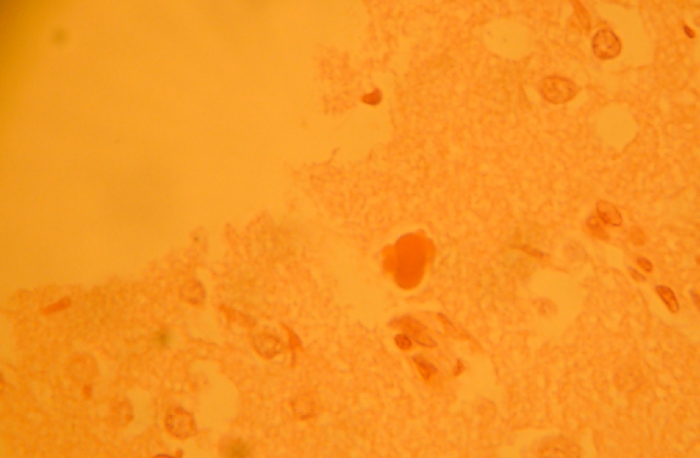

Candida auris: A Fungal Superbug

September 20, 2018 Natalia Ciesielska

Introduction: In 2009, a 70-year-old woman in Tokyo, Japan was hospitalized with an ear infection that did not seem to improve with antibiotics [4].